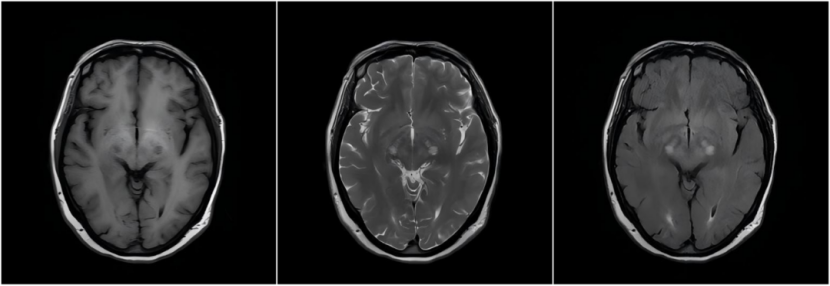

为尽快破解诊断难题,减轻患者负担,西藏自治区医院神经内科通过远程会诊平台,连线我院神经内科专家团队。会诊过程中,神经内科周东主任医师等资深专家,与主治团队进行了深入的在线交流与讨论。专家结合患者病史、体征及辅助检查,特别是针对其肝脏功能状况与神经系统症状的关联性进行了细致分析,一致明确诊断患者为“获得性肝脑变性(AHCD)”,并为其制定了包括病因治疗、症状控制、营养支持及长期随访在内的个体化、系统化治疗方案。